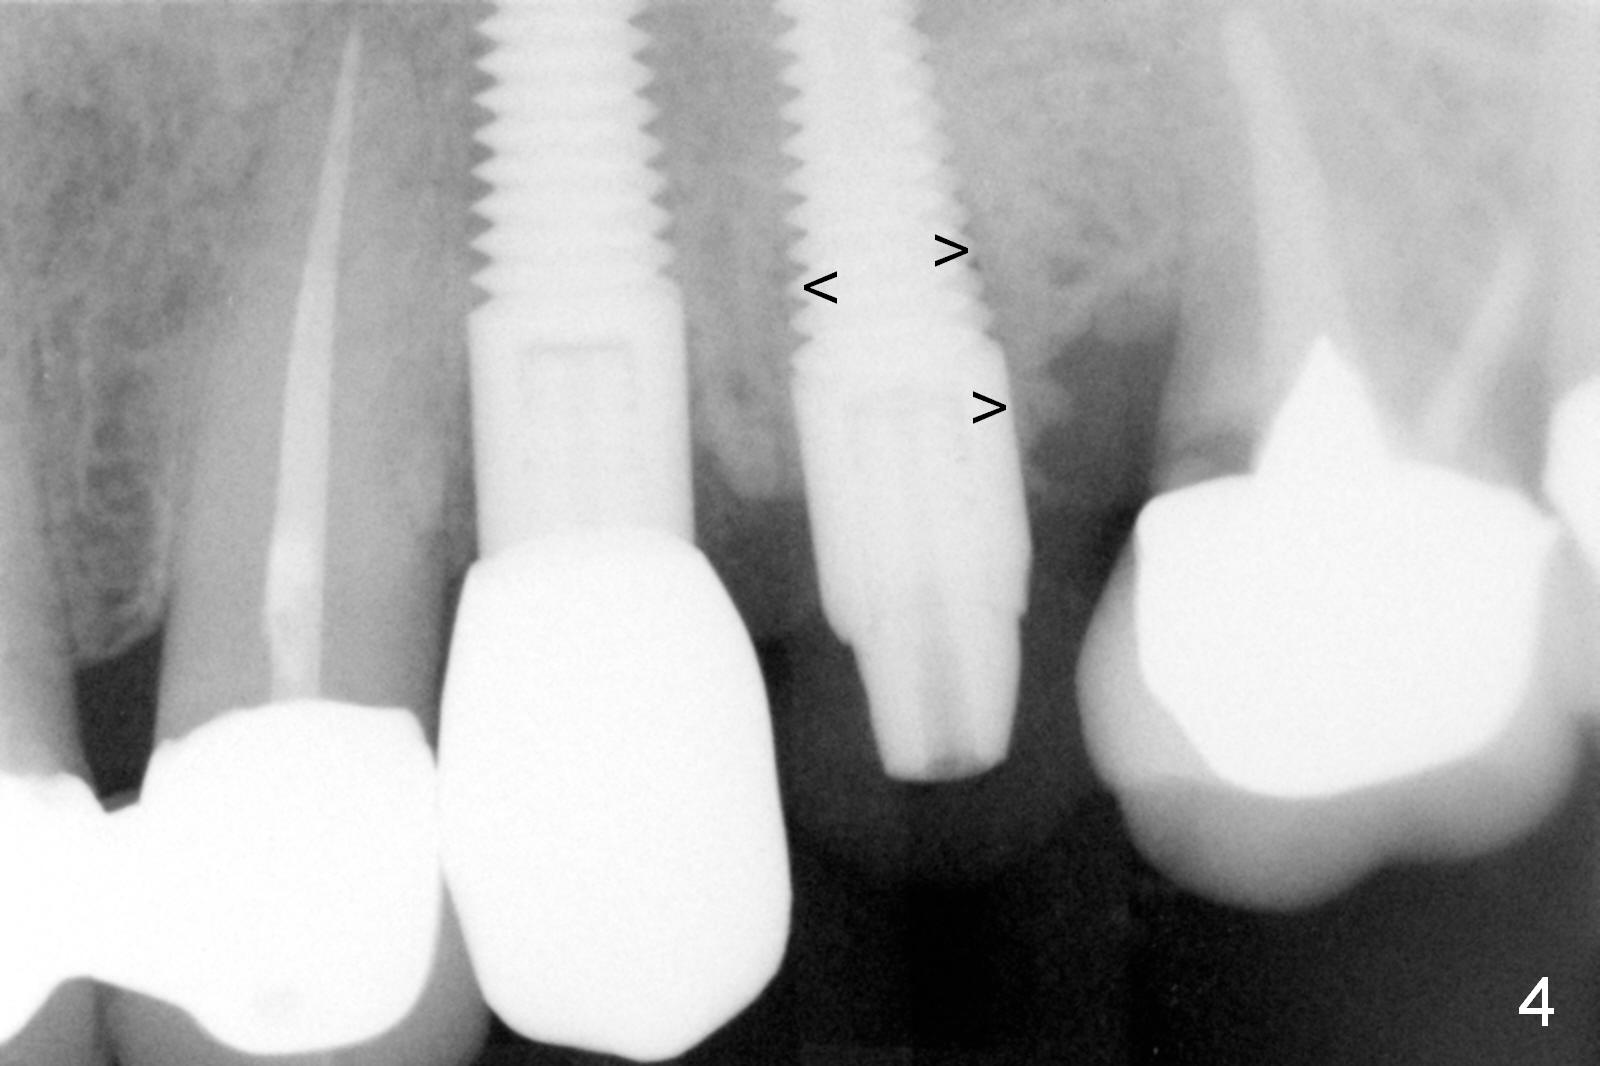

The distal threads appear not covered by the bone 2.5 months postop (Fig.11 >). His oral hygiene is excellent with healthy gingiva around the implant when the permanent crown is cemented. Panoramic X-ray is taken 3 years and 1 year 5 months post cementation for #12 and 13, respectively (Fig.12). The bone density around the implant at #13 increases 2 years 6 months post cementation (Fig.13 *). The bone density of the sinus lift (Fig.14,15 *) is essentially the same as that of the bone buccal (B) and palatal to the implant 4.5 years post cementation. The upper left panel is a 3D view from the sinus.